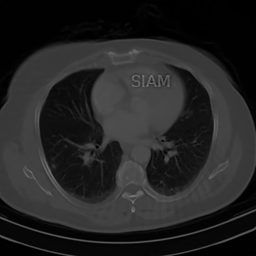

Fig. 2 presents an example of this result. In this figure, the ‘Mickey Mouse’ detail xmi𝒩(A)subscript𝑥mi𝒩𝐴x_{\mathrm{mi}}\in\mathcal{N}(A), whereas the ‘Thumb’ detail xthsubscript𝑥thx_{\mathrm{th}} has relatively large measurements, i.e., |||Axth|||0\mbox{$|\!|\!|$}Ax_{\mathrm{th}}\mbox{$|\!|\!|$}\gg 0. The NN is trained to recover the image xbr+xth+xmisubscript𝑥brsubscript𝑥thsubscript𝑥mix_{\mathrm{br}}+x_{\mathrm{th}}+x_{\mathrm{mi}}. As a result, it incorrectly transfers the detail xmisubscript𝑥mix_{\mathrm{mi}}, while the detail xthsubscript𝑥thx_{\mathrm{th}} is handled correctly (i.e., it is not transferred). Fig. 4 shows another example of this effect. In this case, A𝐴A is a subsampled Radon transform, which models a CT imaging scenario. Here, the NN is trained to recover the detail image x+xDet𝑥subscript𝑥Detx+x_{\mathrm{Det}}, and as a result, it incorrectly transfer the detail xDetsubscript𝑥Detx_{\mathrm{Det}} when recovering the detail-free image x𝑥x.

x+xDet𝑥subscript𝑥Detx+x_{\mathrm{Det}} x𝑥x

Refer to caption Refer to caption

Ψ(A(x+xDet))Ψ𝐴𝑥subscript𝑥Det\Psi(A(x+x_{\mathrm{Det}})) Ψ(Ax)Ψ𝐴𝑥\Psi(Ax)

Refer to caption \begin{overpic}[width=433.62pt]{plots/sample_00101_pred.png} \put(45.0,82.0){\color[rgb]{1,0,0}\definecolor[named]{pgfstrokecolor}{rgb}{1,0,0}\vector(1,-2){6.0}} \end{overpic}

Figure 4: (Hallucinations due to detail transfer). A NN Ψ:mN:Ψsuperscript𝑚superscript𝑁\Psi\colon\mathbb{R}^{m}\to\mathbb{R}^{N} is trained to accurately recover CT images and the image x+xDet𝑥subscript𝑥Detx+x_{\mathrm{Det}} with the “SIAM” detail insert, as shown in the first column. This causes the NN to incorrectly transfer the “SIAM” detail when reconstructing the clean image x𝑥x from measurements Ax𝐴𝑥Ax, just as described by Theorem 4.1. In this experiment the matrix A𝐴A is a subsampled Radon transform which samples 50 equally spaced angles, and the detail xDemsubscript𝑥Demx_{\mathrm{Dem}} is designed such that 0<AxDet2Ax20subscriptnorm𝐴subscript𝑥Detsuperscript2much-less-thansubscriptnorm𝐴𝑥superscript20<\|Ax_{\mathrm{Det}}\|_{\ell^{2}}\ll\|Ax\|_{\ell^{2}}.